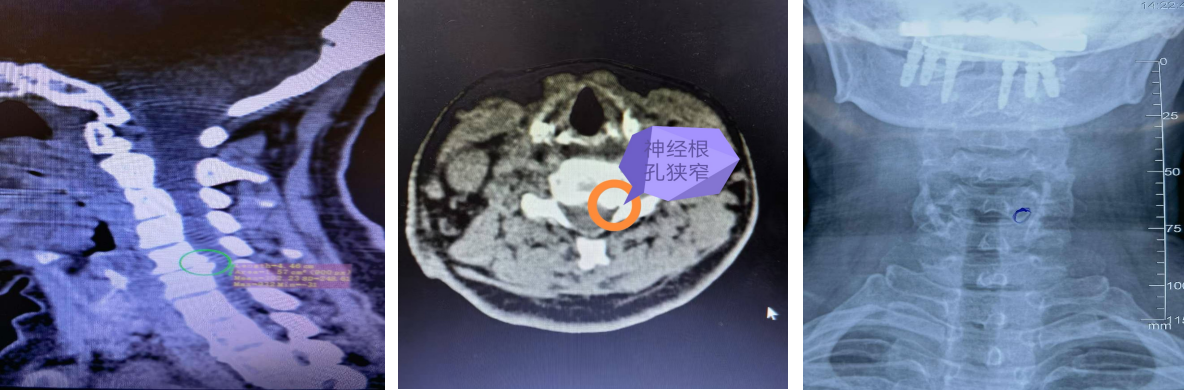

衢州骨伤科医院脊柱外科主任林俊接诊后,详细询问病史并结合CT、磁共振检查结果,确定郑女士的情况比较特殊,症状是由第5第6颈椎椎体后缘增生,压迫神经根引起的,增生的骨质其压迫C6左侧神经根孔,是典型的“神经根型颈椎病”表现,符合微创手术的适应症。

经过详细检查和评估,衢州骨伤科医院脊柱外科团队决定采用微创颈椎后路椎间孔切开术也叫Key-hole来为她进行治疗。

术中出血不到5毫升,切口长度约1厘米左右。术后患者左侧肩颈部和左上肢疼痛症状即刻得到明显缓解,经影像复查显示,保留了大部分侧块关节突关节,稳定性良好。